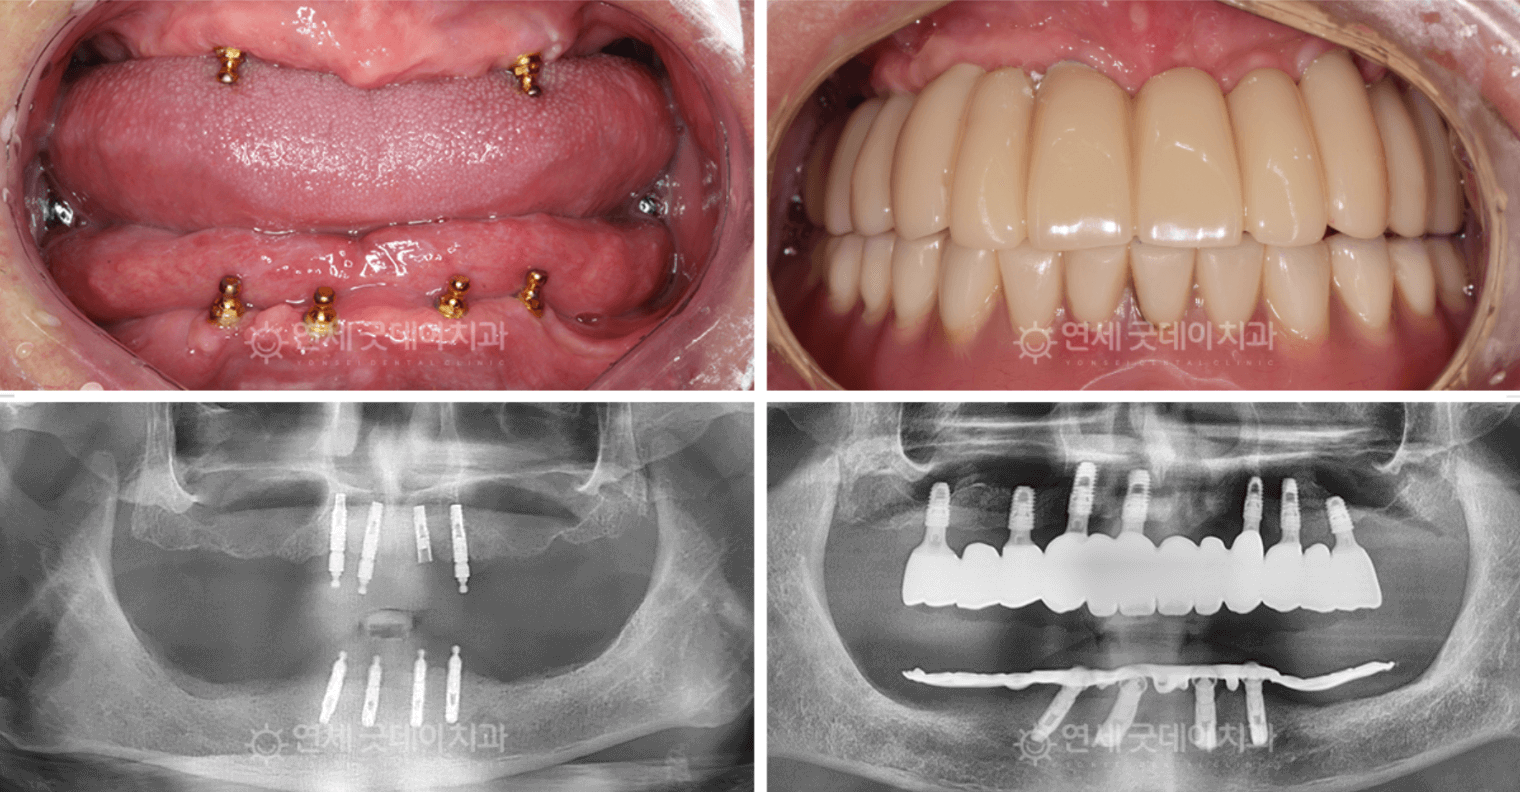

全口植牙 —— 適合缺失大部分或全部牙齒的患者,提供完整解決方案。

All-on-4 植牙 —— 僅需四支植體即可重建整排牙齒的革命性技術。

骨移植與上顎竇提升術 —— 植牙前的預備治療,為植體建立堅實的基礎。

進行完整的牙科檢查,包括 3D 影像與數位X光,以評估骨骼結構與口腔健康狀況。

02. 植體植入

透過先進的手術技術,將植體精準地植入顎骨中。

隨著時間推移,植體會與骨頭結合(骨整合作用),確保長期穩定。

03. 癒合期與專屬修復

癒合完成後,為患者安裝客製化的牙冠、牙橋或假牙,

確保功能完整且外觀自然。